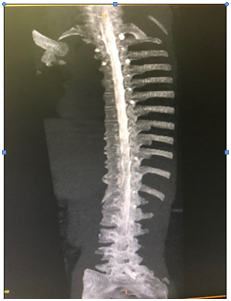

Her imaging showed multiple foraminal cysts; see in Figure 6.

Figure 6 Myelogram of the spine shows multilevel, at times bilateral Tarlov Cysts.

The left L 2/3 nerve root sleeve demonstrates an intra- foraminal Tarlov cyst measuring approximately 7mm indiameter with active extravasation of contrast in the surrounding tissues along the left para spinal muscles.

L 1/2 nerve root sleeve demonstrates bilateral small Tarlov’s cysts, the cyst on the left measures up to 4mm in diameter; the right measures up to 2.5mm in diameter; see Figures 7a & 7b.